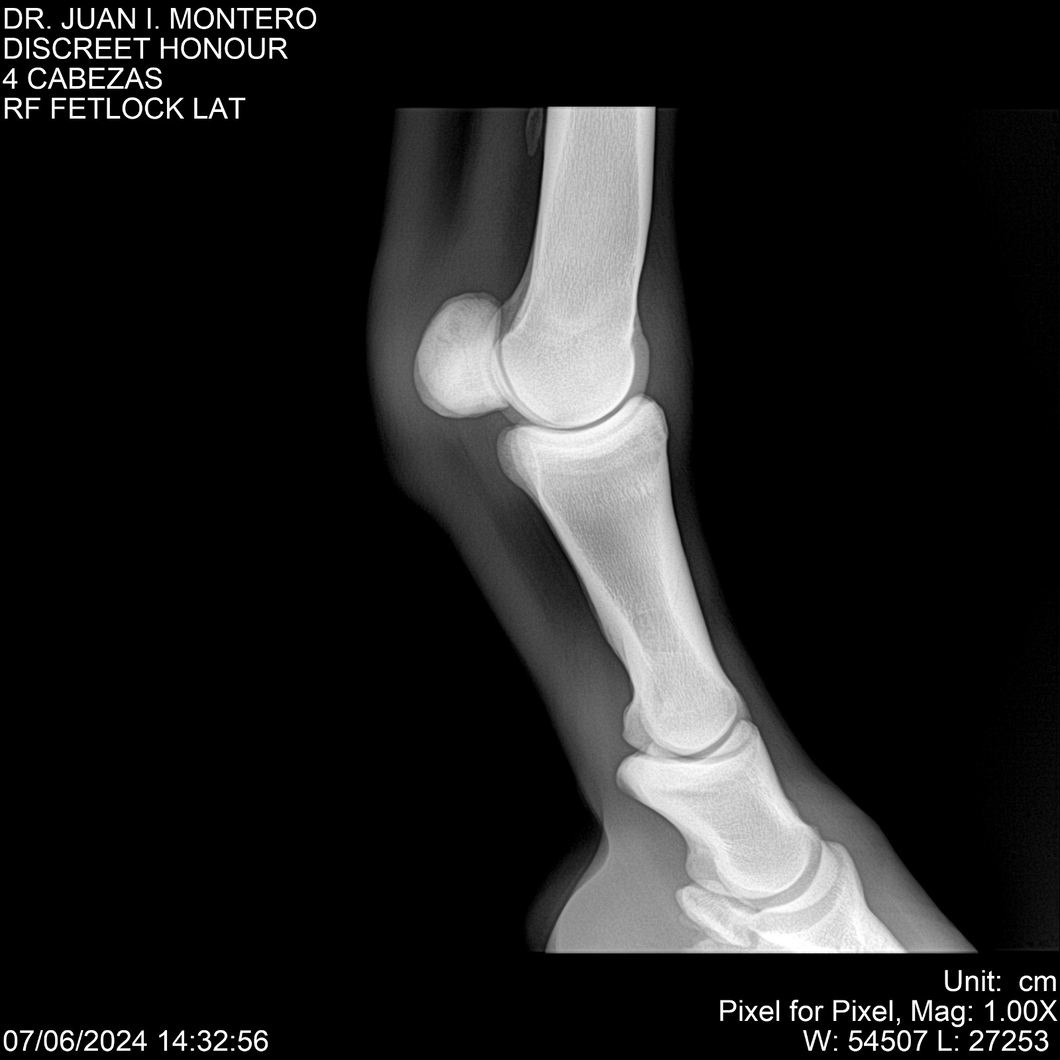

LOTE 6, DISCREET HONOUR 🔥 🔥 🔥 Lote Anterior Volver al remate Lote Siguiente Ficha Contacto Montevideo - Ficha del Lote Identificador: #281093 Categoría: Yeguarizos Montevideo - 82 Visualizaciones ClicData Contacto Empresa: Abelenda N. R., Walter Hugo Nombre*: Teléfono* : E-mail* : Mensaje Enviar Registrese gratis Este contenido Exclusivo está disponible sólo para usuarios registrados Ingresar